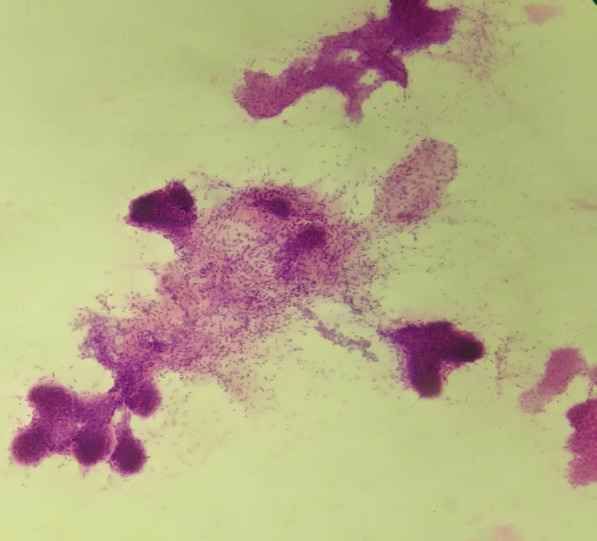

Background & objective: Phyllodes tumor (PT) is a rare fibroepithelial tumor of the breast exhibiting varied clinicopathologic behavior, ranging from benign to borderline to frankly malignant, based on the presence of infiltrative margins, stromal overgrowth, stromal atypia, cellularity, and mitotic activity. In this study, a detailed cytomorphological study of cases of PT with the clinical and histological correlation was performed.

Methods: A cytomorphological study of 17 cases of histologically proven PT diagnosed between Jan 2014 and July 2021 was done retrospectively. Relevant data including age at the time of diagnosis, the duration of illness, presenting symptoms, personal and family history, tumor size, tumor localization, and surgical procedure were obtained. A detailed cytomorphological assessment of stromal and epithelial components was performed, and further histological correlation was obtained for each case.

Results: Age of the patients ranged from 25 to 65 years old. The chief complaint was a palpable breast mass in all patients. The mean size of the lump was 11.86 cm. A complete cytohistological concordance was achieved among malignant cases. Stromal metaplasia was observed in only one case of benign phyllodes tumor, which was chondroid differentiation, and malignant heterologous component as fibrosarcomatous differentiation in one of the malignant PTs. Each of the benign and malignant phyllode tumors ductal carcinoma in situ (DCIS) of its epithelial component was seen in one case.

Conclusion: Phyllodes should be considered in differential diagnosing of any rapidly growing breast lump. Breast imaging has limited role in diagnosis of phyllode tumors. FNAC or trucut biopsy is mandatory in preoperative diagnosis. An extended follow-up is needed in all cases.